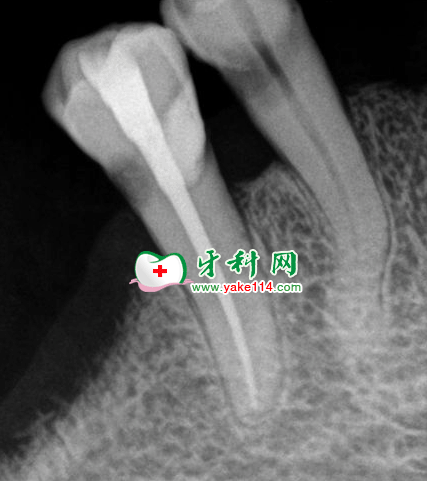

EDTA、0.9%氯化鈉注射液反復(fù)擴(kuò)洗至F3,隔濕,吹干,必蘭根充糊劑+牙膠尖充填,X線示恰充,磷酸鋅水門汀墊底,復(fù)合樹脂充填,常規(guī)醫(yī)囑。

根充后效果。單根牙治療比較簡(jiǎn)單,相對(duì)難度較低,對(duì)臨床操作技術(shù)的練習(xí)很有幫助。